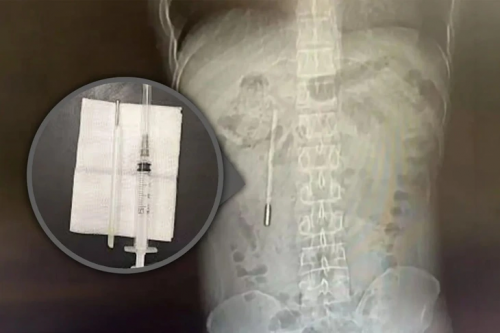

Chiếc nhiệt kế đã nằm trong bụng người đàn ông suốt 20 năm sau khi nuốt phải từ năm 12 tuổi - Ảnh: SCMP |

Kết quả chụp X-quang phát hiện một dị vật trong tá tràng, được các bác sĩ xác định là chiếc nhiệt kế thủy ngân. Do đầu nhọn của nhiệt kế cắm trực tiếp vào thành ruột, bệnh nhân đối mặt nguy cơ cao bị thủng ruột và xuất huyết nội nghiêm trọng.

Các bác sĩ phẫu thuật lấy dị vật ra ngoài chỉ trong 20 phút. Đây là ca can thiệp đòi hỏi độ chính xác cao do nhiệt kế lưu lại trong cơ thể quá lâu và nằm gần ống mật, tiềm ẩn nguy cơ tổn thương thành ruột trong quá trình thao tác.

Chiếc nhiệt kế sau khi được lấy ra vẫn còn nguyên vẹn, song các vạch đo nhiệt độ đã phai mờ theo thời gian.